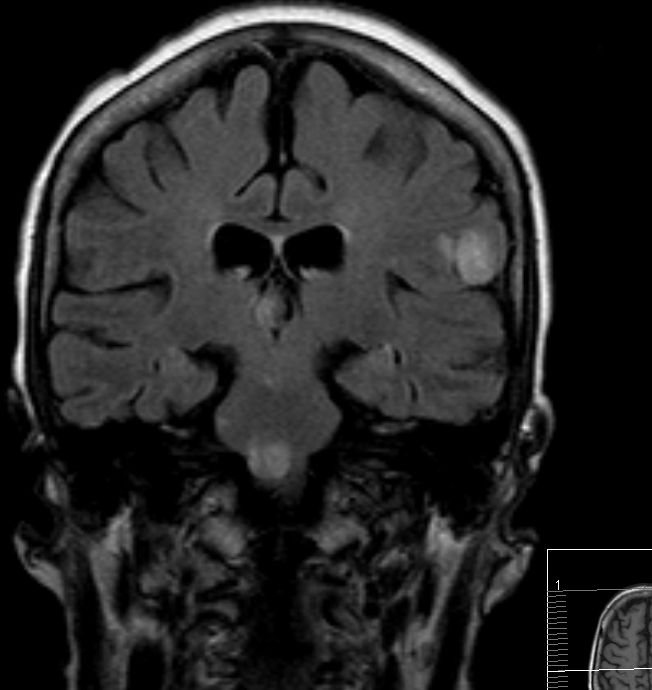

Hirnmetastase

Hirnmetastase links occipital mit ausgeprägtem Ödem.

Im MRT Metastase im rechten Amygdala. Zusätzlich weitere Metastasen.